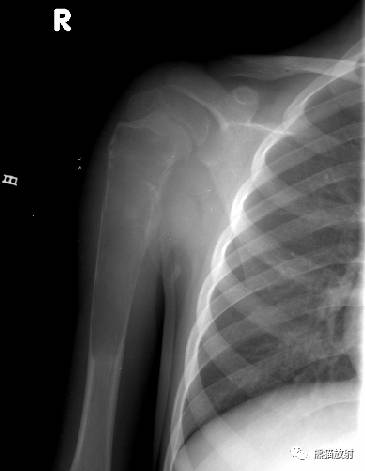

↓ 肱骨上段ABC(男7岁)